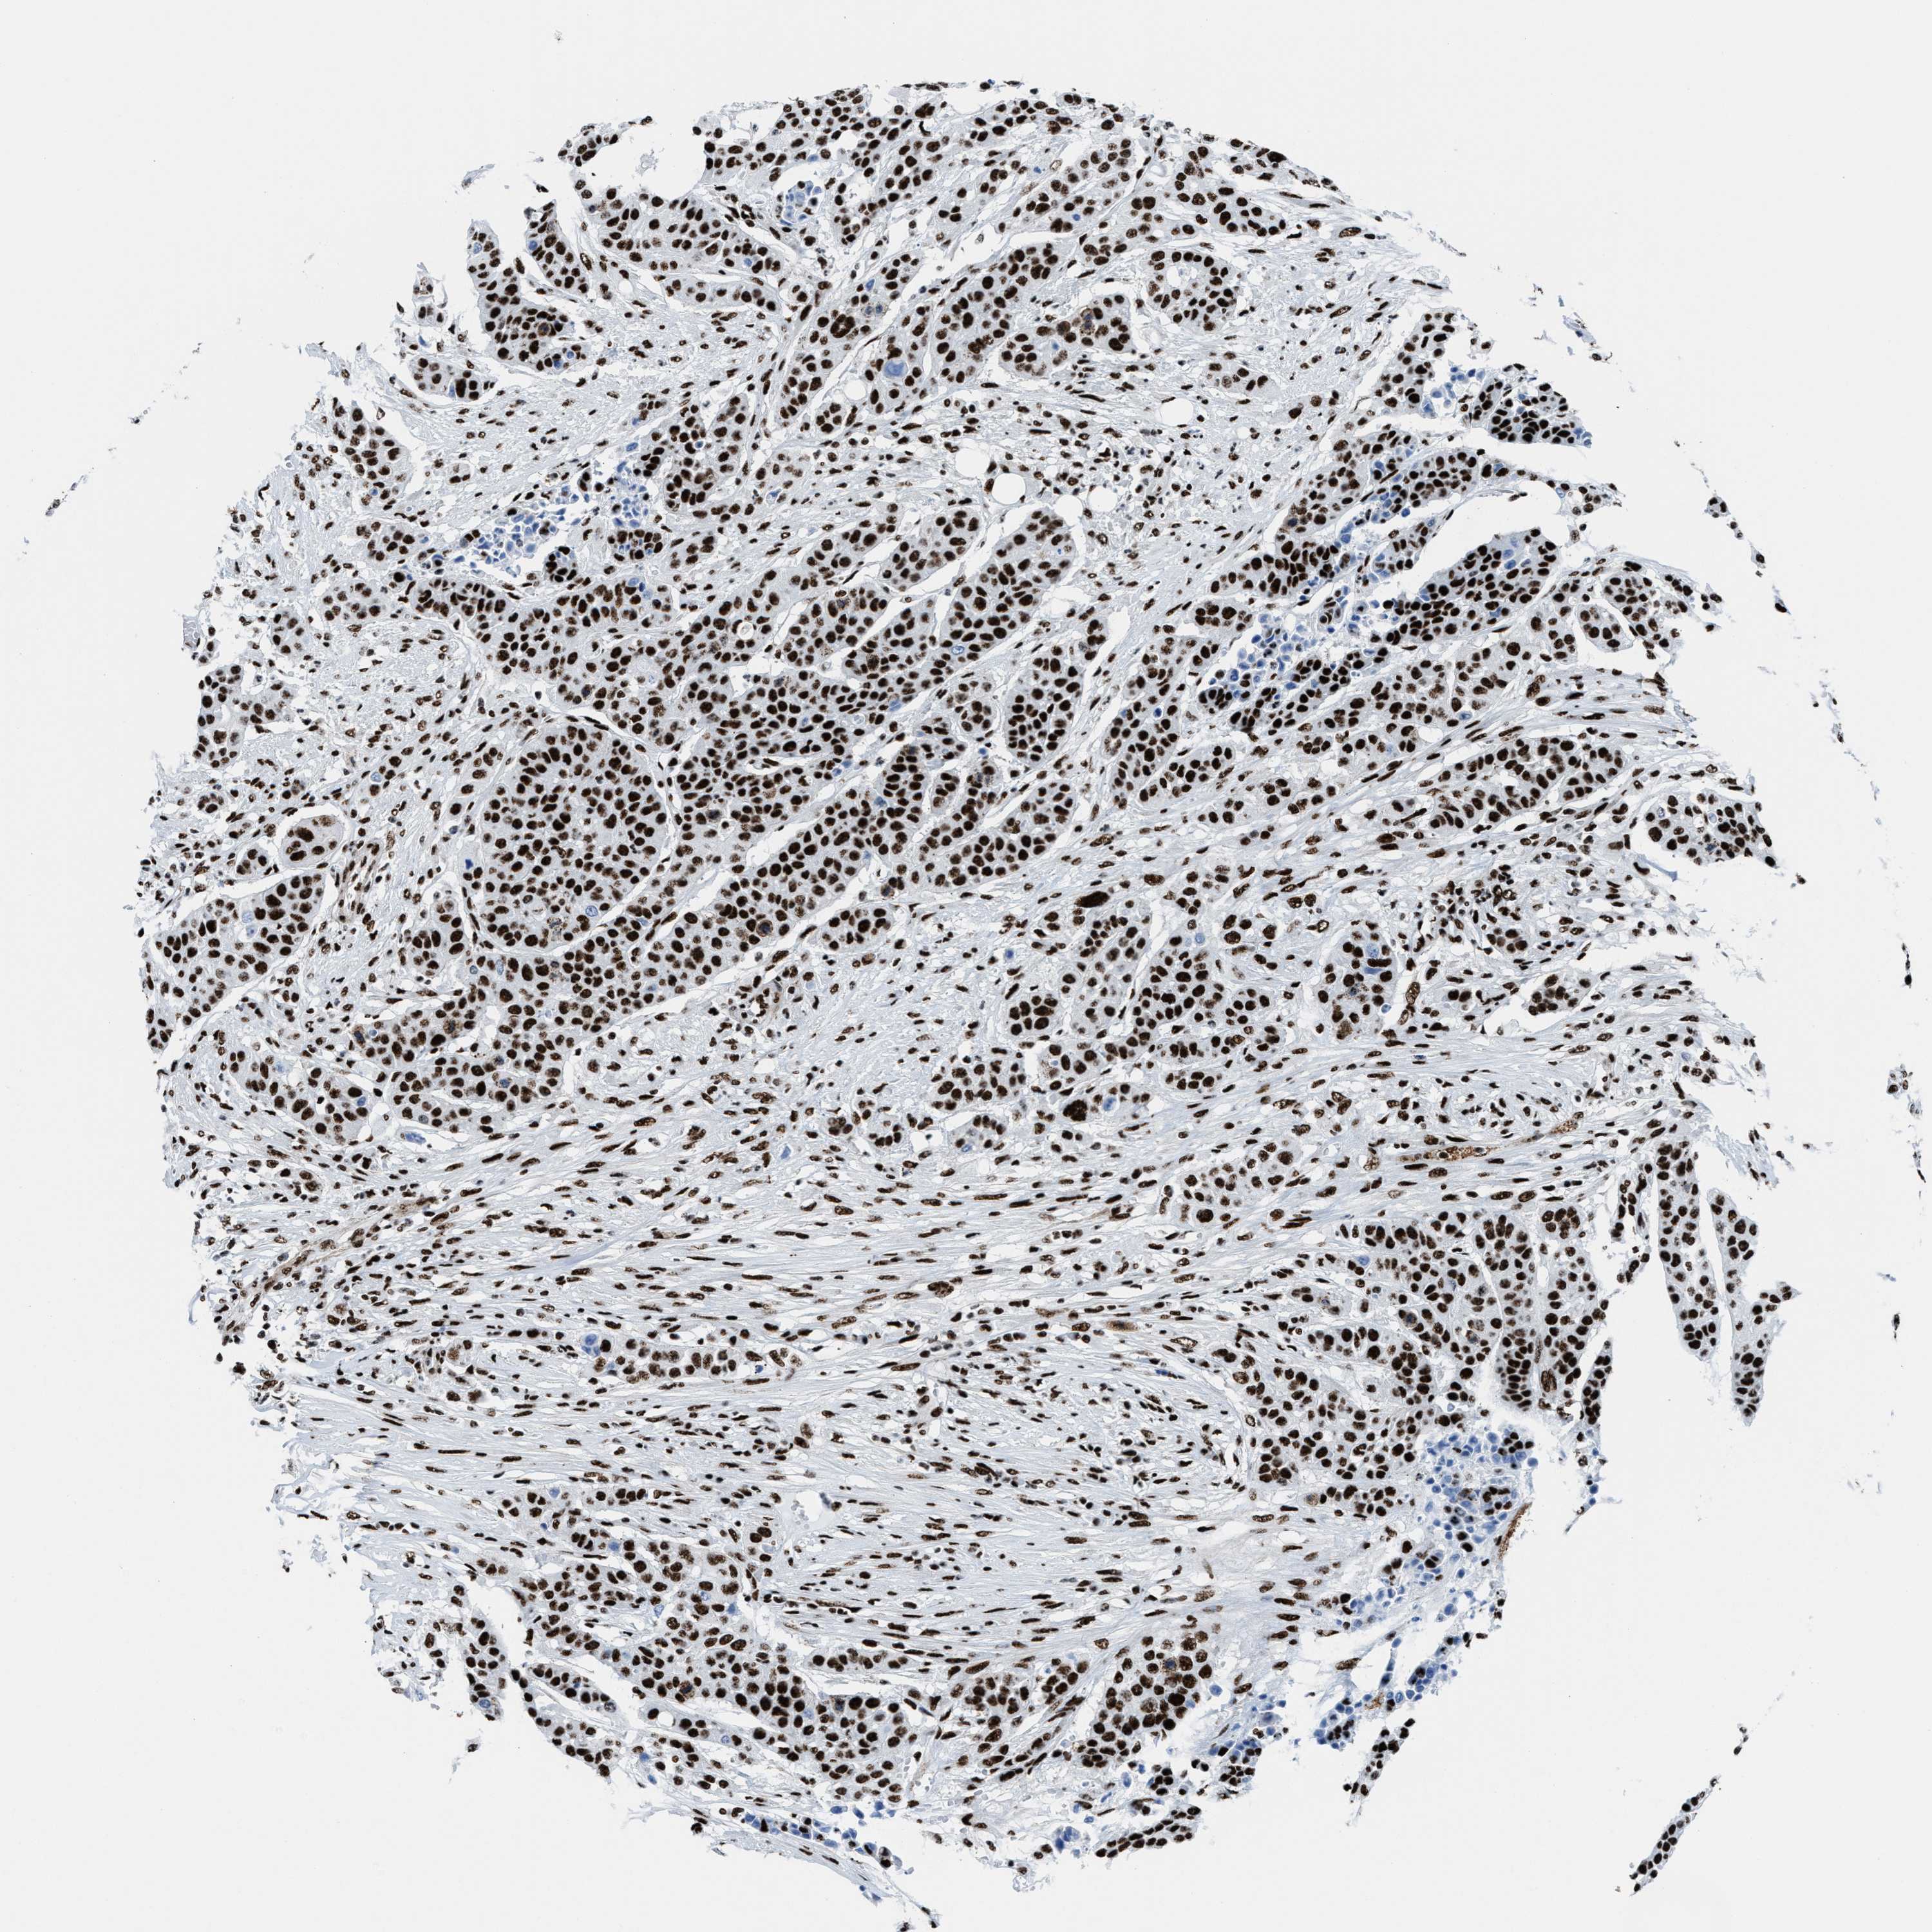

UROTHELIAL CANCER - Protein expressioni

A mouse-over function shows sample information and annotation data. Click on an image to view it in a full screen mode. Samples can be filtered based on level of antibody staining by selecting one or several of the following categories: high, medium, low and not detected. The assay and annotation is described here.

Antibody stainingi

Antibody staining in the annotated cell types in the current human tissue is reported as not detected, low, medium, or high, based on conventional immunohistochemistry profiling in selected tissues. This score is based on the combination of the staining intensity and fraction of stained cells.

Each image is clickable and will lead to virtual microscopy that enables deeper exploration of all samples and also displays staining intensity scores, fraction scores and subcellular localization as well as patient and tissue information for each sample.

Antibody HPA054094

Antibody HPA054559

Antibody CAB022069

Staining

High

Medium

Low

Not detected

Intensity

Strong

Moderate

Weak

Negative

Quantity

>75%

75%-25%

<25%

None

Location

Nuclear

Cytoplasmic/membranous

Cytoplasmic/membranous,nuclear

Urothelial carcinoma, High grade

Urothelial carcinoma, NOS

Urothelial carcinoma, Low grade